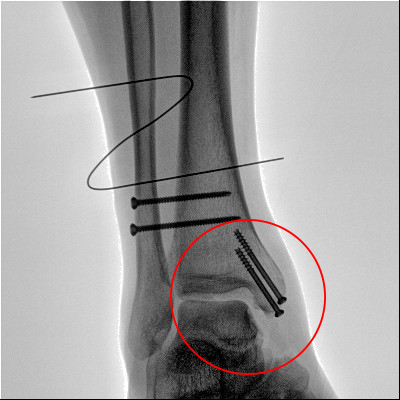

【醫(yī)療科普】之外踝骨折

外踝骨折